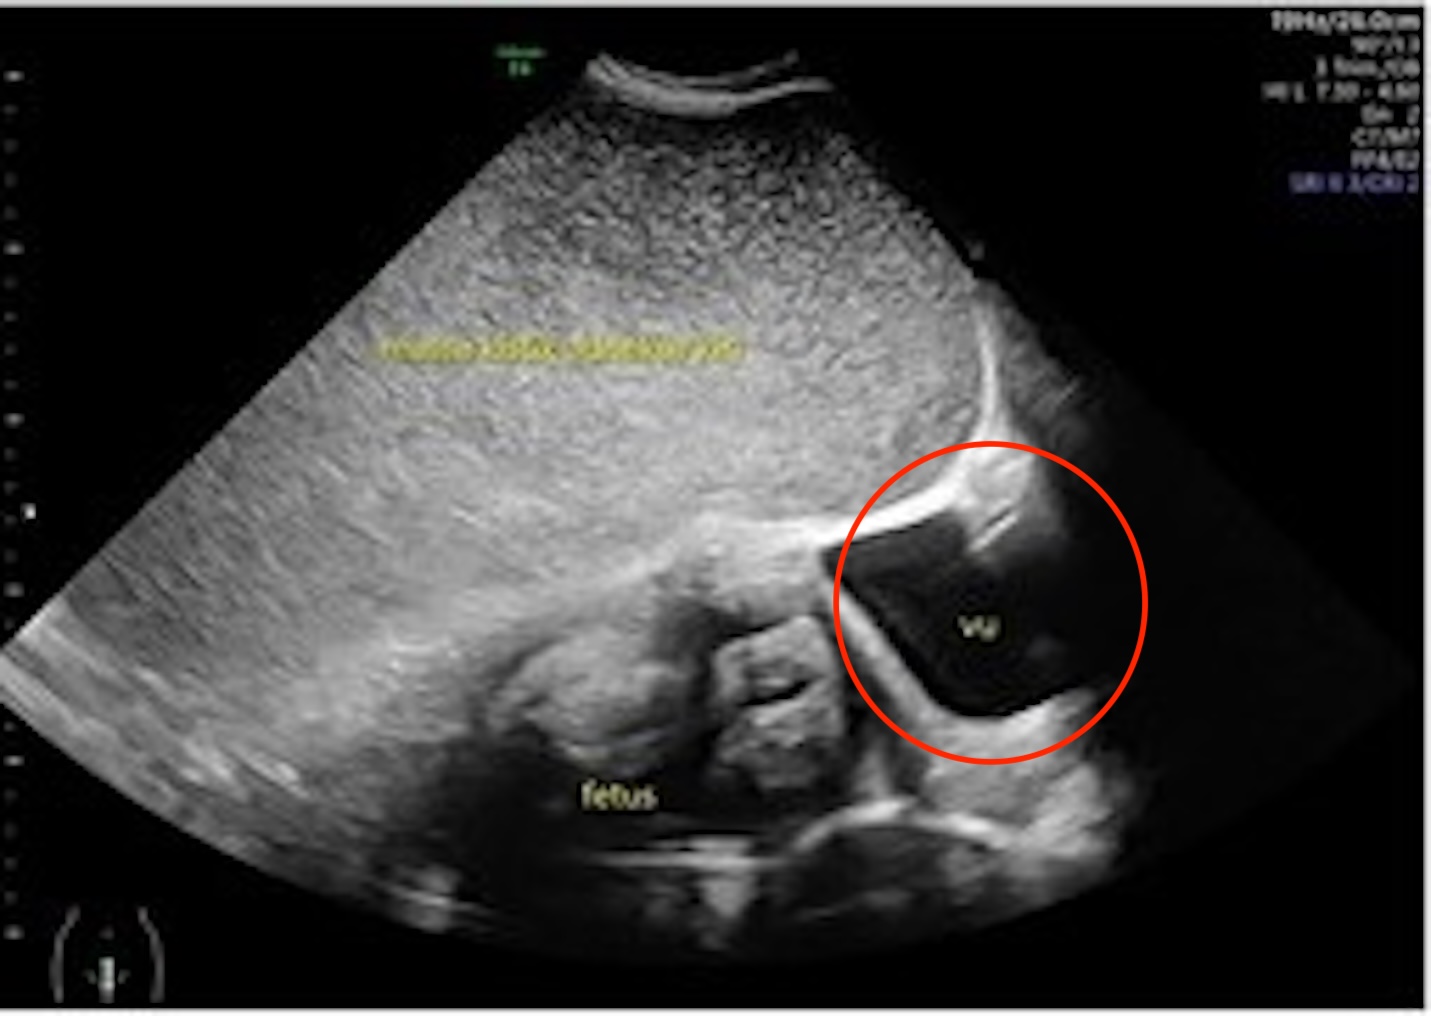

Những hình ảnh được chia sẻ bởi Need To Know cho thấy hình ảnh siêu âm khối u trước khi cắt bỏ.

Hình minh họa cho thấy vị trí của u nang, bao phủ một phần tử cung và đẩy sang một bên.

Sau lần khám bệnh thứ hai, các bác sĩ phát hiện thai nhi bắt đầu chậm phát triển – được cho là do u nang đẩy tử cung về phía bên phải bụng.

Bốn tuần sau, các bác sĩ đã tiến hành phẫu thuật cho người mẹ và phát hiện ra khối u khổng lồ xuất phát từ buồng trứng trái, chứa 11 lít dịch.

Trong khi đó, các bác sĩ đã nghiên cứu khối u nang và phát hiện nó có đường kính 35cm và lành tính.